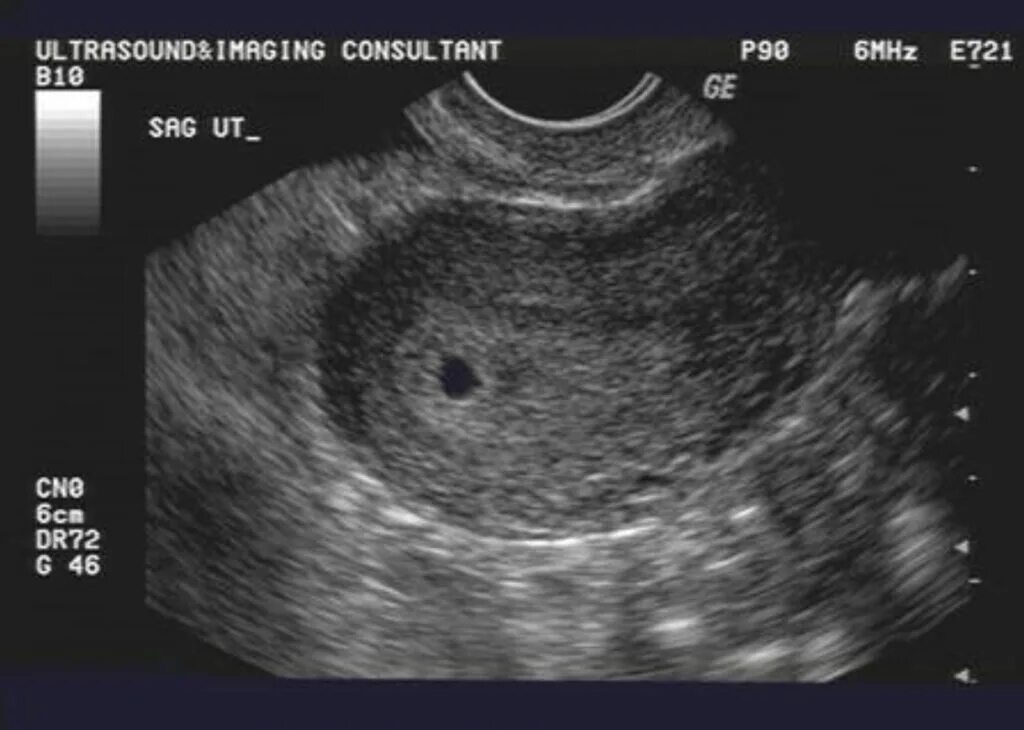

Беременность 4 недели что происходит с плодом